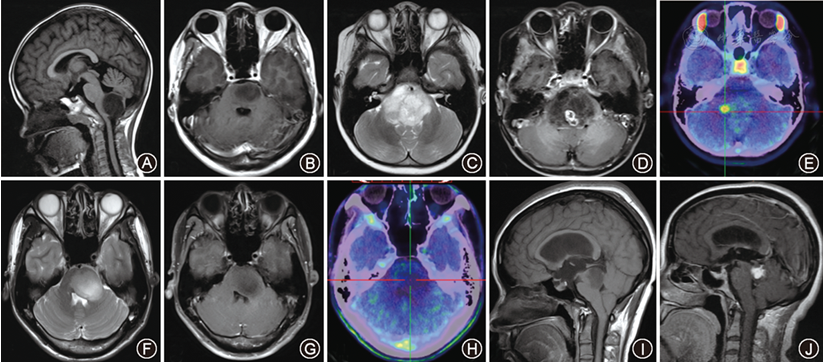

(2)弥漫内生型桥脑胶质瘤(DIPG):该肿瘤预后一般较差,它位于脑干核心区域(下图),传统开颅手术风险极高,通常通过临床和影像学特征诊断,手术(尤其是切除手术)指征极低,主要依靠放疗和化疗,目前针对该肿瘤的临床试验也在积极开展中。

即使孩子的胶质瘤处于功能区也不意味着没有手术希望。手术切除率大多取决于肿瘤的位置和类型。简单来说,基本上有两种类型的胶质瘤,一种是生长在中枢神经组织的局灶性肿瘤(下图B),这意味着肿瘤生长紧凑,而且与正常组织有明确的边界,将有极大可能实现全切。另一种是弥漫性的胶质瘤,它大多散布在大脑或脊髓内,没有清晰的边界(下图F-H)。在这种情况下,一般无法达到很高的切除率。